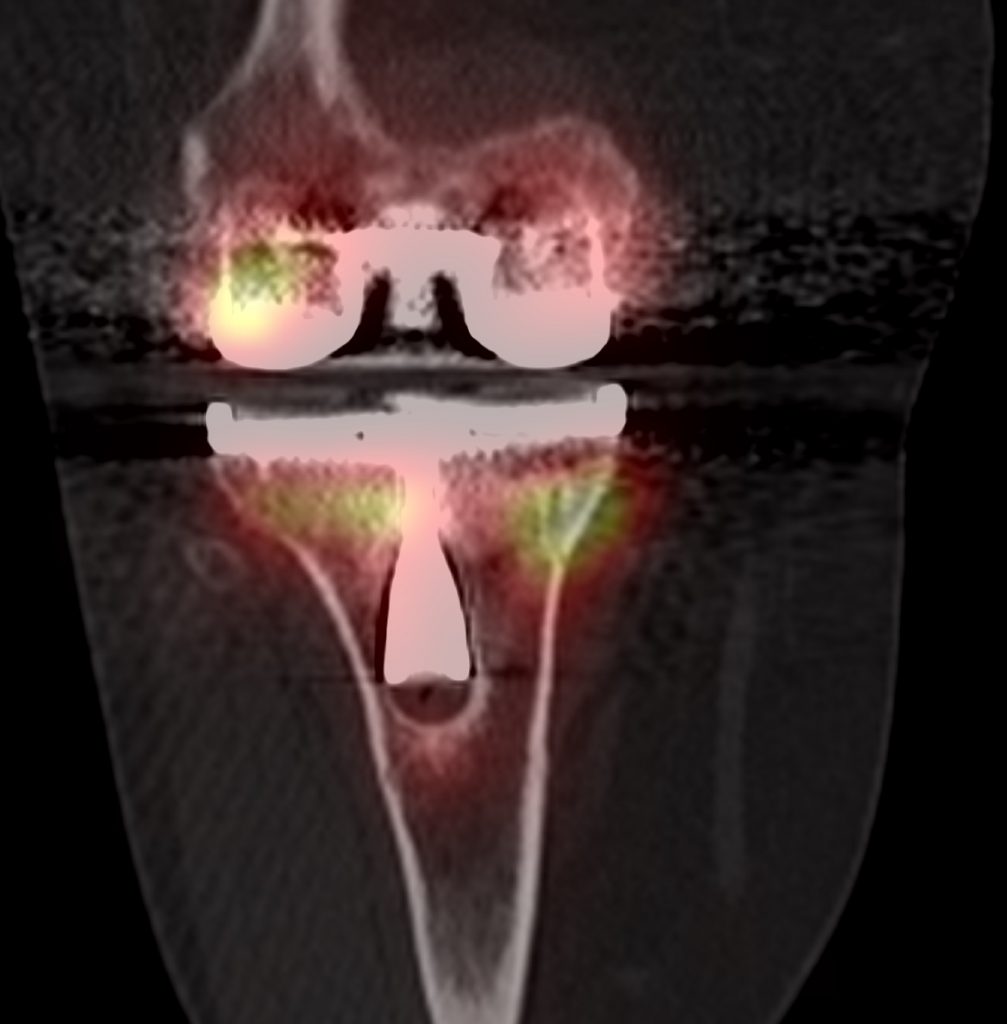

The tibial component is loose when there is focal increased tracer uptake at the sites of maximal mechanical stress; usually at the tip of the tibial component and at the contralateral tibial tray. Loosening of the femoral component is often associated with increased uptake adjacent to the posterior aspects of the condyles, adjacent to the bone prosthesis interface. The CT component will show a periprosthetic lucency that is greater than 2mm in width, with irregular margins, at the site of increased bone uptake.

Infected prostheses usually have increased activity in dynamic and blood pool phases throughout the bone surrounding the infected prosthesis. On SPECT-CT there is diffuse increased uptake around the bone prosthesis interface, with periosteal reaction, soft tissue oedema, soft tissue abscesses or joint effusions.